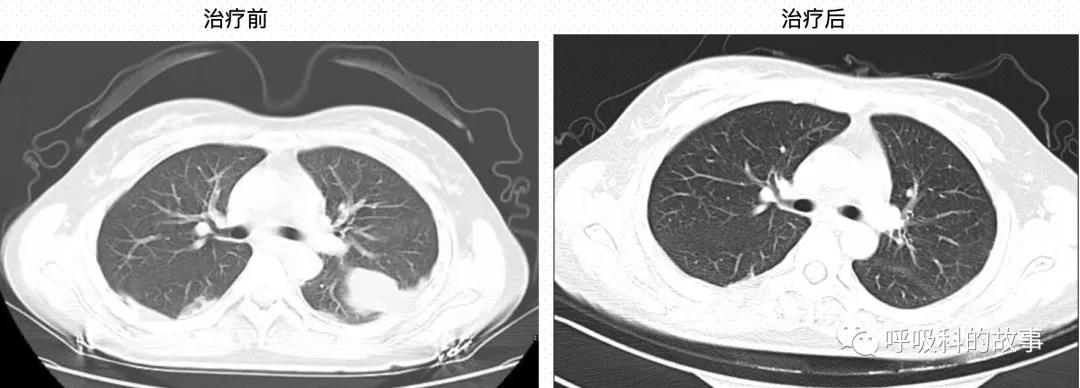

立即给患者家属告病危,使用上低分子肝素抗凝,还请血管外科会诊,建议用下腔静脉滤器置入术,但是患者由于经济原因拒绝了。医生们密切观察病情变化,期待着她能早日康复。终于一周后,患者痊愈,D 二聚体降到了1920 μg/L,胸部病变消失。

患者门诊随访半年,目前状态良好。